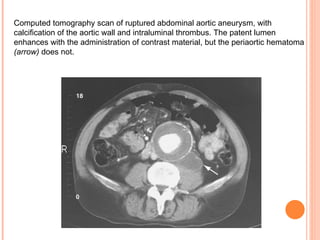

Computed tomography scan of ruptured abdominal aortic aneurysm, with calcification of the aortic wall and intraluminal thrombus. The patent lumen enhances with the administration of contrast material, but the periaortic hematoma   ( arrow )   does not .

Computed tomography scanof ruptured abdominal aortic aneurysm, with calcification of the aortic wall and intraluminal thrombus. The patent lumen enhances with the administration of contrast material, but the periaortic hematoma ( arrow ) does not .